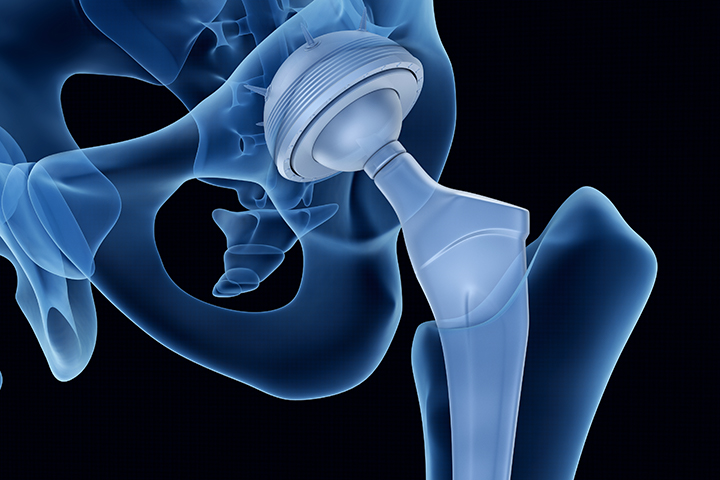

Whether you’re dealing with chronic hip pain, limited mobility, or a recent injury, Iowa Ortho offers comprehensive hip care to help you regain comfort in your life. Our orthopedic specialists diagnose and treat a wide range of hip conditions using the latest non-surgical and surgical techniques. With advanced imaging, personalized treatment plans, and on-site physical therapy, we’re here to support your recovery every step of the way. Discover expert hip care at Iowa Ortho and get back to doing what you love.